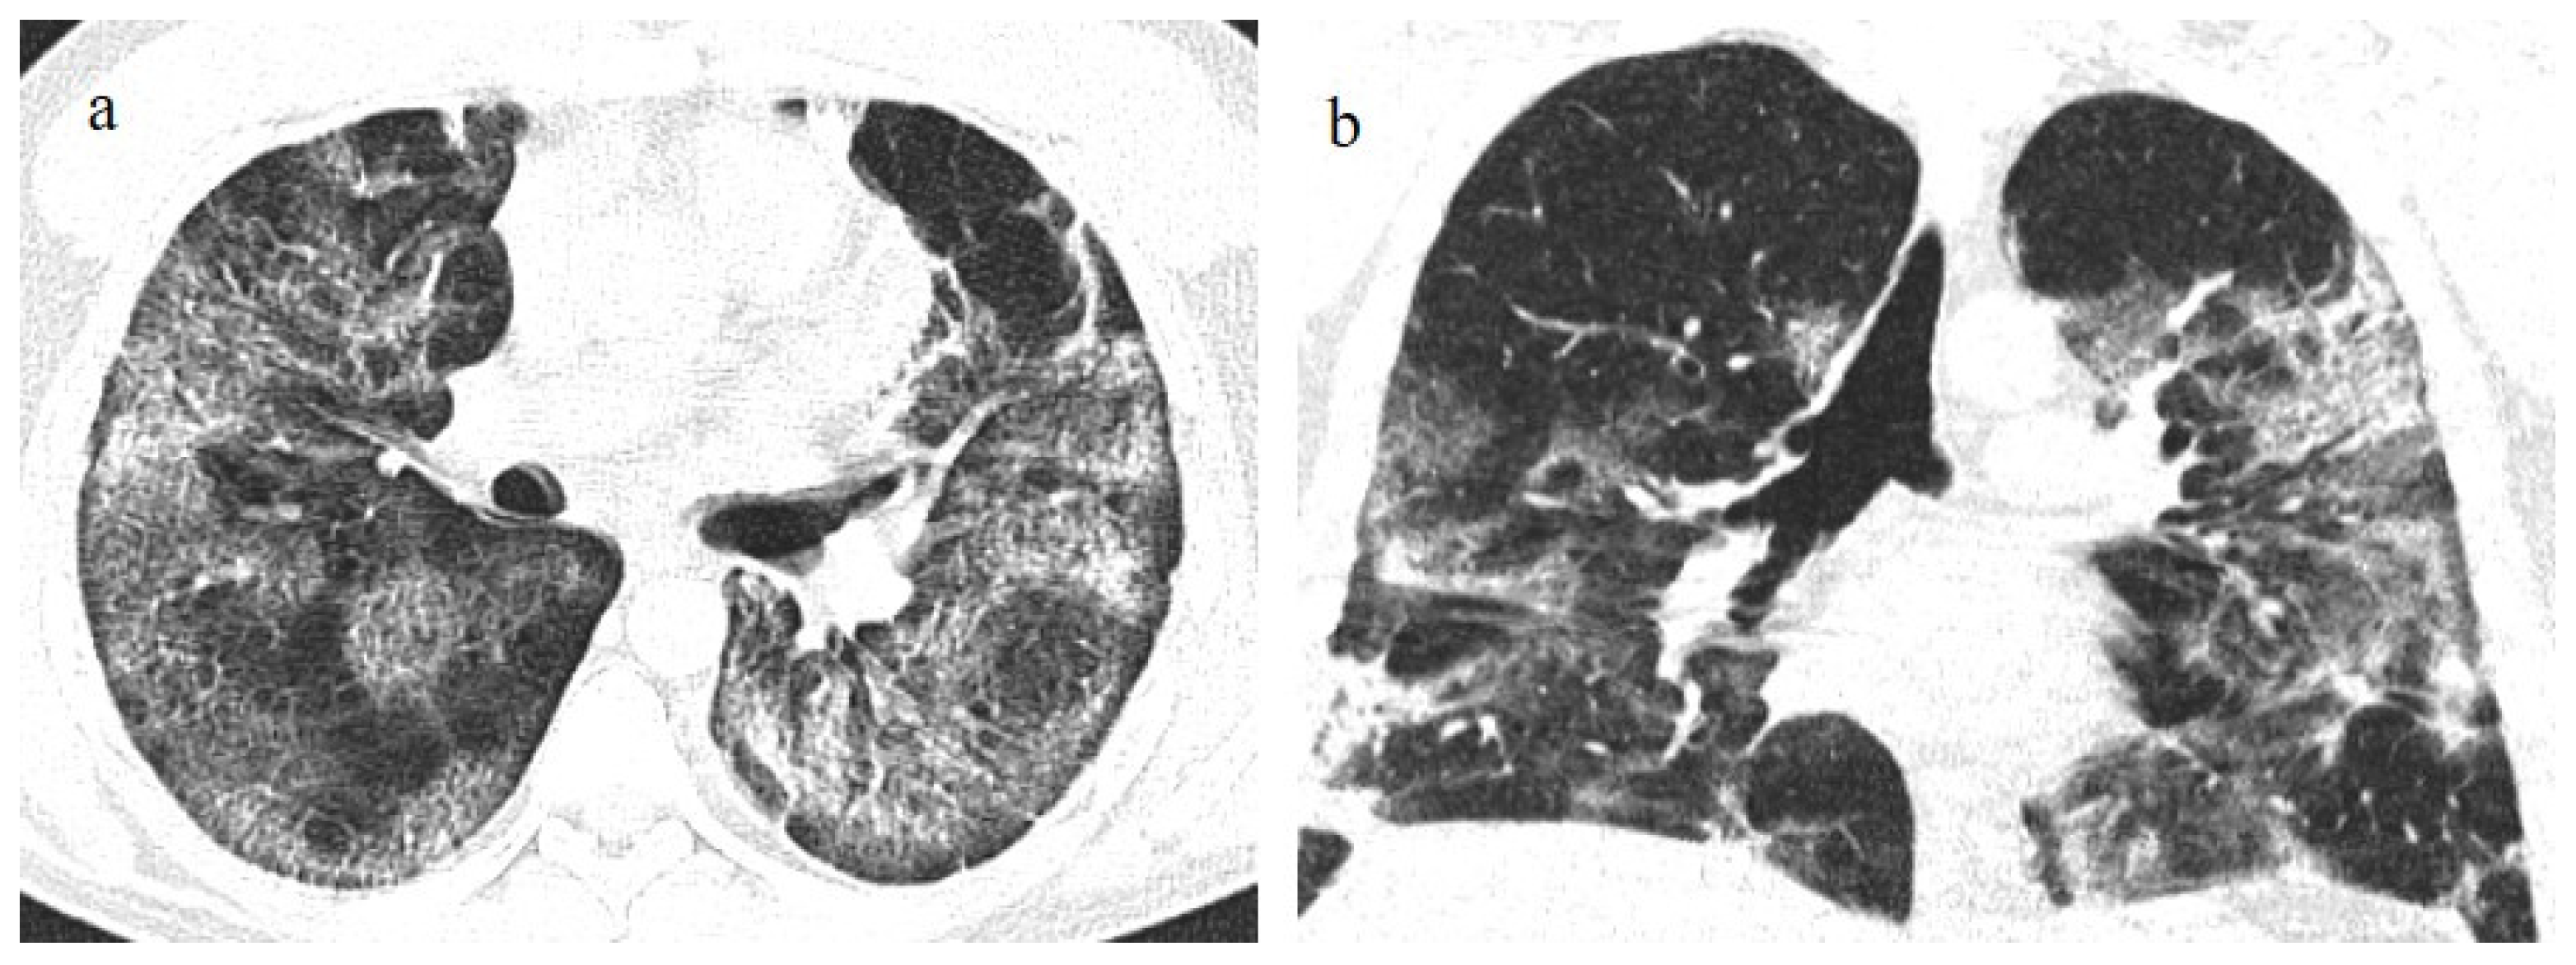

- Kanne, J.P.; Little, B.P.; Schulte, J.J.; Haramati, A.; Haramati, L.B. Long-term Lung Abnormalities Associated with COVID-19 Pneumonia. Radiology 2023, 306, e221806. [Google Scholar] [CrossRef]

- Han, X.; Fan, Y.; Alwalid, O.; Zhang, X.; Jia, X.; Zheng, Y.; Shi, H. Fibrotic Interstitial Lung Abnormalities at 1-year Follow-up CT after Severe COVID-19. Radiology 2021, 301, E438–E440. [Google Scholar] [CrossRef]

- Watanabe, A.; So, M.; Iwagami, M.; Fukunaga, K.; Takagi, H.; Kabata, H.; Kuno, T. One-year follow-up CT findings in COVID-19 patients: A systematic review and meta-analysis. Respirology 2022, 27, 605–616. [Google Scholar] [CrossRef]

- Bocchino, M.; Lieto, R.; Romano, F.; Sica, G.; Bocchini, G.; Muto, E.; Capitelli, L.; Sequino, D.; Valente, T.; Fiorentino, G.; et al. Chest CT–based Assessment of 1-year Outcomes after Moderate COVID-19 Pneumonia. Radiology 2022, 305, 479–485. [Google Scholar] [CrossRef] [PubMed]

- Cocconcelli, E.; Bernardinello, N.; Giraudo, C.; Castelli, G.; Giorgino, A.; Leoni, D.; Petrarulo, S.; Ferrari, A.; Saetta, M.; Cattelan, A.; et al. Characteristics and Prognostic Factors of Pulmonary Fibrosis After COVID-19 Pneumonia. Front. Med. 2022, 8, 823600. [Google Scholar] [CrossRef] [PubMed]